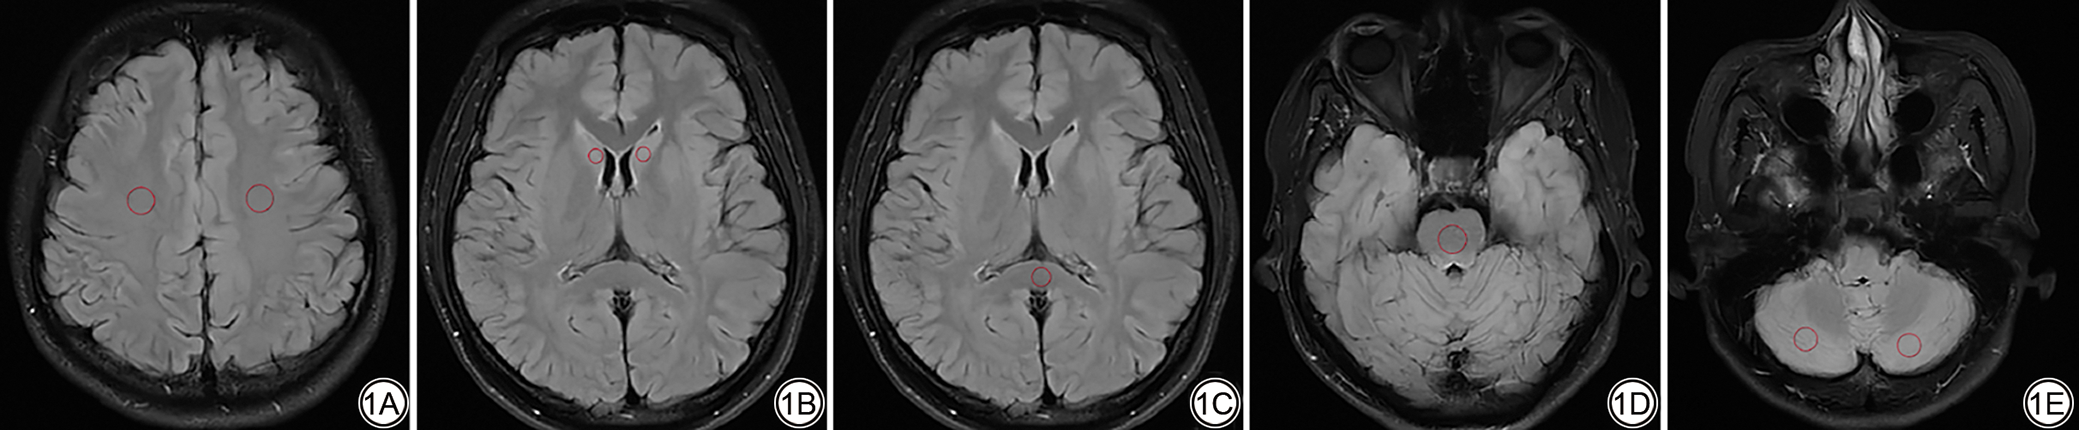

各组图像定性评价结果详见表4图3。PI-DL4组在图像锐利度、噪声和整体图像质量均优于NDL、PI-DL2和PI-DL3组(两两比较P<0.05)(图4)。PI-DL4与PI-DL3组在灰白质对比度、病变显示以及诊断信心差异无统计学意义(P>0.05);PI-DL2与NDL组在所有定性指标差异均无统计学意义(P>0.05);四组图像在伪影方面的评分差异无统计学意义(P>0.05)。另外,少数患者DL等级4病变边缘对比度下降(图5)。

图5  男,53岁,经临床随访证实为黑色素瘤脑转移。5A~5D:采用不同算法重建的常规和加速T2-FLAIR图像。5A:NDL组常规T2-FLAIR传统重建图像;5B:PI-DL2组快速T2-FLAIR DL重建等级2图像;5C:PI-DL3组快速T2-FLAIR DL重建等级3图像;5D:PI-DL4组快速T2-FLAIR DL重建等级4图像;5E:T2加权图像;5F:T1加权图像;5G:增强T1加权图像;5H:弥散加权图像。T2-FLAIR可见高信号病变,弥散受限,增强序列可见明显强化。PI-DL4组与其他图像相比,左侧病变(黄箭)边缘较为模糊。这是因为病变边缘与噪声特征相似,为获得更高SNR,将病变极少一部分当作噪声进行平滑处理,导致病变边缘模糊。T2-FLAIR: 液体衰减反转恢复;PI:并行采集;SNR:信噪比;DL:深度学习。

Fig. 5  Male, 53 years old, Clinical follow-up confirmed brain metastases from melanoma. 5A to 5D: Conventional and accelerated T2-FLAIR images reconstructed with different deep learning algorithms. 5A: Conventional T2-FLAIR image with traditional reconstruction in the NDL group. 5B: Fast T2-FLAIR image reconstructed with DL level 2 (PI-DL2 group). 5C: Fast T2-FLAIR image reconstructed with DL level 3 (PI-DL3 group). 5D: Fast T2-FLAIR image reconstructed with DL level 4 (PI-DL4 group). 5E: T2-weighted image. 5F: T1-weighted image. 5G: T1-weighted contrast-enhanced image. 5H: diffusion-weighted image. High signal mass lesions can be seen on the T2-FLAIR image, restricted diffusion with obvious enhancement on contrast-enhanced imaging. Compared with other imaging modalities, the margin of the left-sided lesion (indicated by the yellow arrow) in PI-DL4 is relatively indistinct. This may be due to the lesion's edge characteristics being similar to noise. To achieve higher SNR, a minimal portion of the lesion was smoothed as noise, resulting in the blurred margin. T2-FLAIR: T2-fluid attenuated inversion recovery; PI: parallel imaging, SNR: signal-to-noise ratio; DL: deep learning.